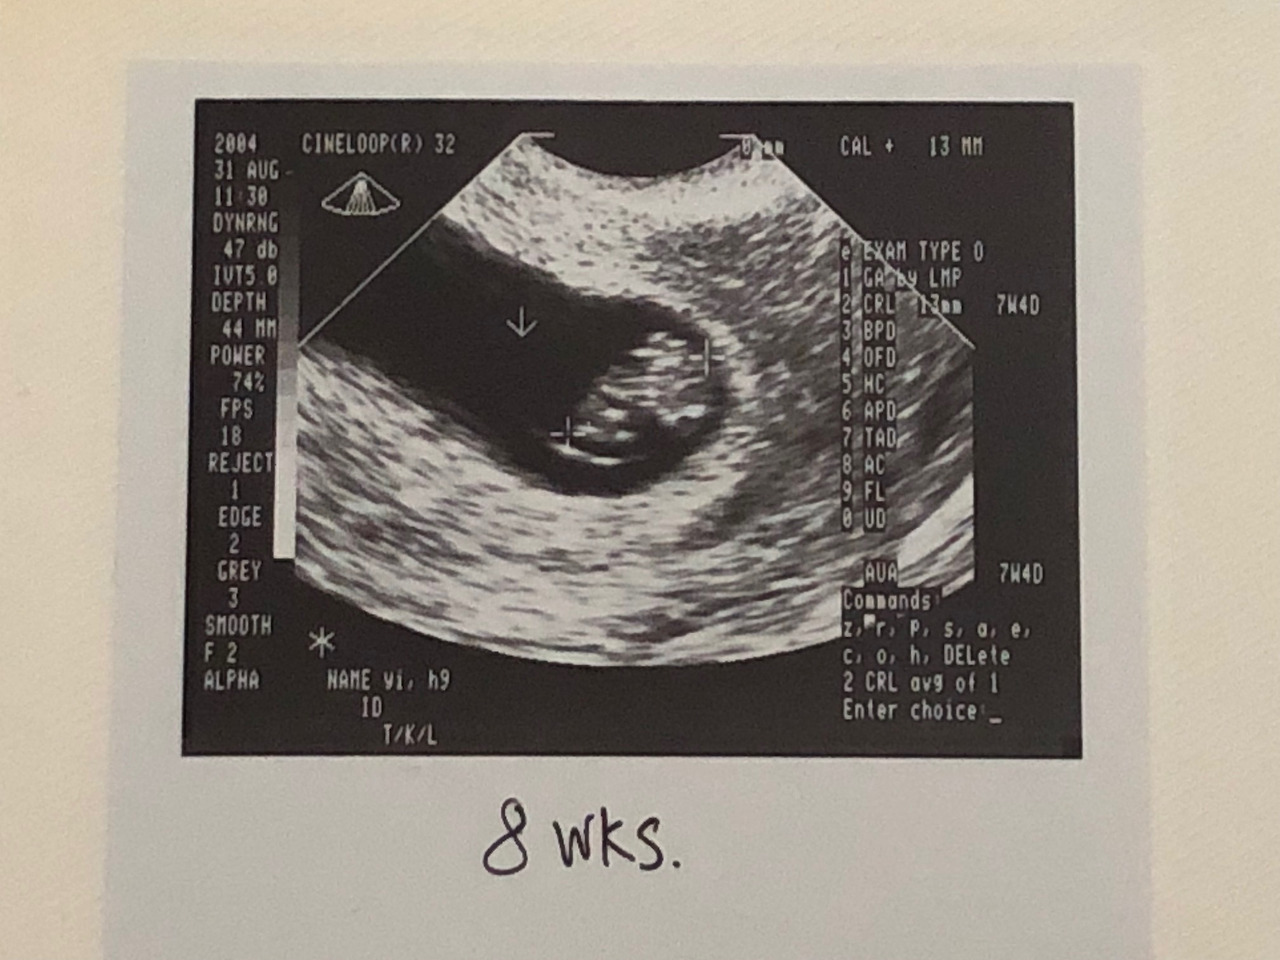

에이브리8.jpg

8주 차에 처음 본 아기의 모습

내가 아빠가 될 거 란다....